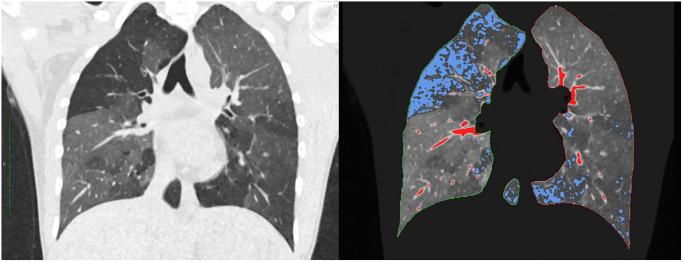

Quantified computed tomography (qCT) is known for correlations with airflow obstruction and fibrotic changes of the lung. However, as qCT studies often focus on diseased and elderly subjects, current literature lacks physiological qCT values during body development. We evaluated chest CT examinations of a healthy cohort, reaching from infancy to adulthood, to determine physiological qCT values and changes during body development.

METHOD

Dose-optimized chest CT examinations performed over the last 3 years using a dual-source CT were retrospectively analysed. Exclusion criteria were age >30 years and any known or newly diagnosed lung pathology. Lung volume, mean lung density, full-width-at-half-maximum and low attenuated volume (LAV) were semi-automated quantified in 151 patients. qCT values between different age groups as well as unenhanced (Group 1) and contrast-enhanced (Group 2) protocols were compared. Models for projection of age-dependant changes in qCT values were fitted.

定量计算机断层扫描(qCT)与气流阻塞和肺部纤维化改变相关。然而,由于 qCT 研究通常集中在患病和老年患者身上,目前的文献缺乏身体发育过程中的生理 qCT 值。我们评估了健康队列的胸部 CT 检查,从婴儿期到成年期,以确定生理 qCT 值和身体发育过程中的变化。

方法

回顾性分析了过去 3 年使用双源 CT 进行的剂量优化胸部 CT 检查。排除标准为年龄>30 岁和任何已知或新诊断的肺部病理学。在 151 名患者中,使用半自动方法对肺容积、平均肺密度、半高全宽和低衰减体积(LAV)进行定量。比较了不同年龄组之间以及未增强(第 1 组)和增强(第 2 组)方案之间的 qCT 值。拟合了用于预测 qCT 值与年龄相关变化的模型。